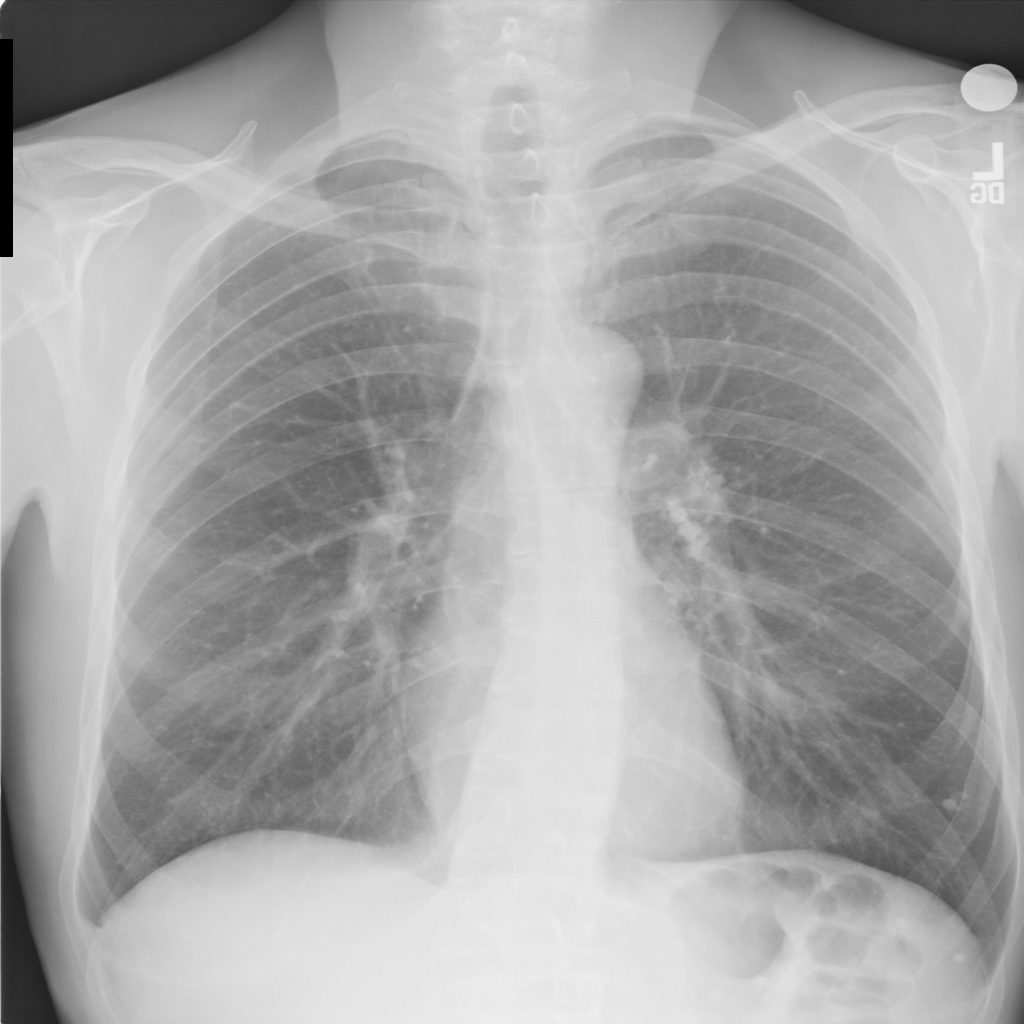

2.4 A Scheme for Lung Structures Enhancement in Real CXR

Once extracted, the lung structures can be added to the original DRR image, allowing for a selective enhancement of lung structures. For the enhancement of real CXR (Fig.1), we first segment the lung area using the segmentation FCNN. We proceed by normalizing the lung area to mean 0, std 0.5. Following the normalization procedure, we use the lung structures extraction FCNN to extract lung structures from the input image (i.e prediction of a “Lung X-ray”). The input CXR image and the synthesized “Lung X-ray” are scaled to the range of [0,1]. We fuse the two images by performing a weighted summation (Eq.6).

IEnhanced=ICXR+wILungXraysubscript𝐼𝐸𝑛𝑎𝑛𝑐𝑒𝑑subscript𝐼𝐶𝑋𝑅𝑤subscript𝐼𝐿𝑢𝑛𝑔𝑋𝑟𝑎𝑦I_{Enhanced}=I_{CXR}+w\cdot I_{LungXray} (6)

In Figure 5 we display example results on a real chest X-ray image. An enhancement weight factor w𝑤w is used to factor the extracted lung image. By controlling w𝑤w, multiple enhancement levels can be achieved.

Refer to caption

Figure 5: NIH Chest X-Ray-14 case #1555 Enhancement Results